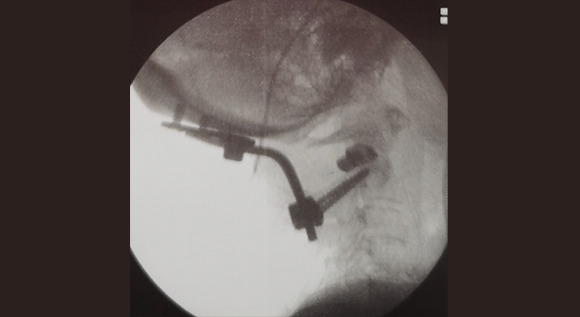

• 寰枢椎脱位椎间融合内固定术 4